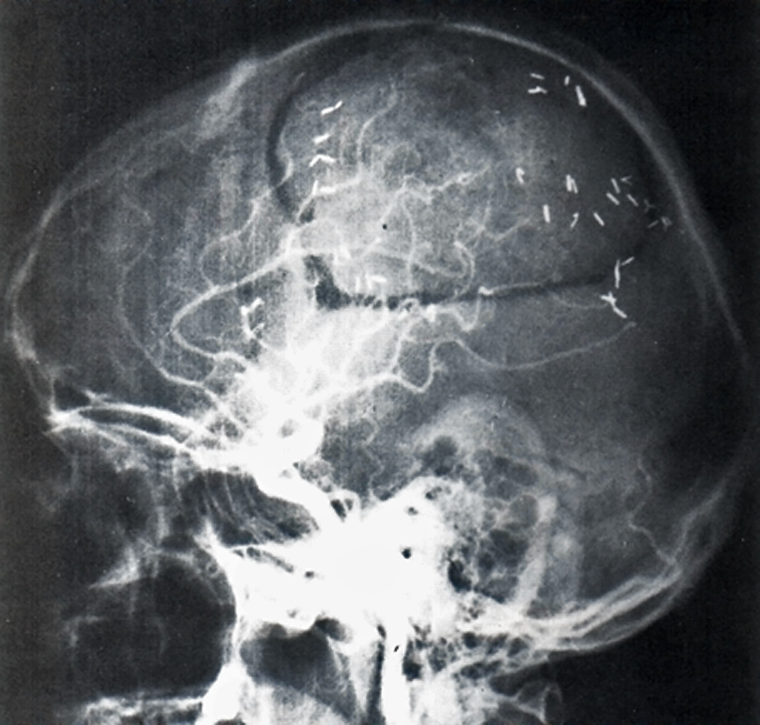

spaceholder redForeign bodies. Hemostatic or other clips in the CNS can move in their position (Figure 18-08). Dislocation by magnetic attraction or torque presents a risk of he­mor­rhage. In other parts of the body, we consider this to be a minimal risk, because af­ter the healing phase of six to eight weeks, fibrosis and encasement of the clip help to keep it in a stable position.

Figura 18-08:

X-ray of a head showing clips after a brain operation: safe or unsafe for MR imaging?